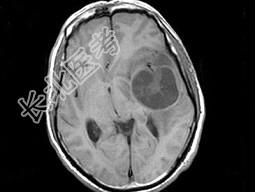

- 单项选择题男,51岁, 1个月前开始头痛,头昏, 根据所提供图像,最可能的诊断是 ( )

A、血管母细胞瘤

B、动脉瘤

C、少枝胶质细胞瘤

D、胶质瘤

E、转移瘤